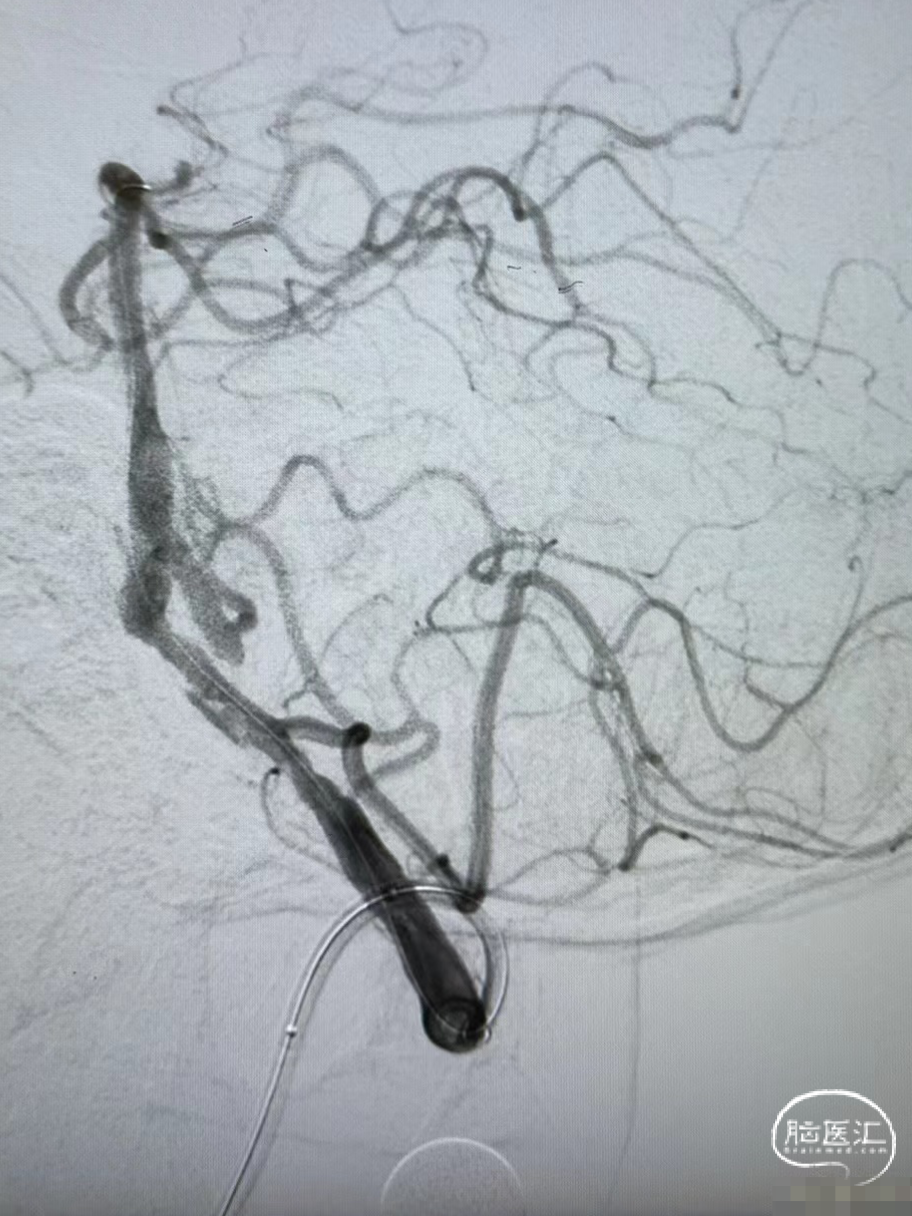

LSCA造影:LVA V2段闭塞。

RVA造影:RVA V4段重度狭窄。

DSA:RVA V4段重度狭窄90%。

术后造影:RV4段狭窄较前明显改善。